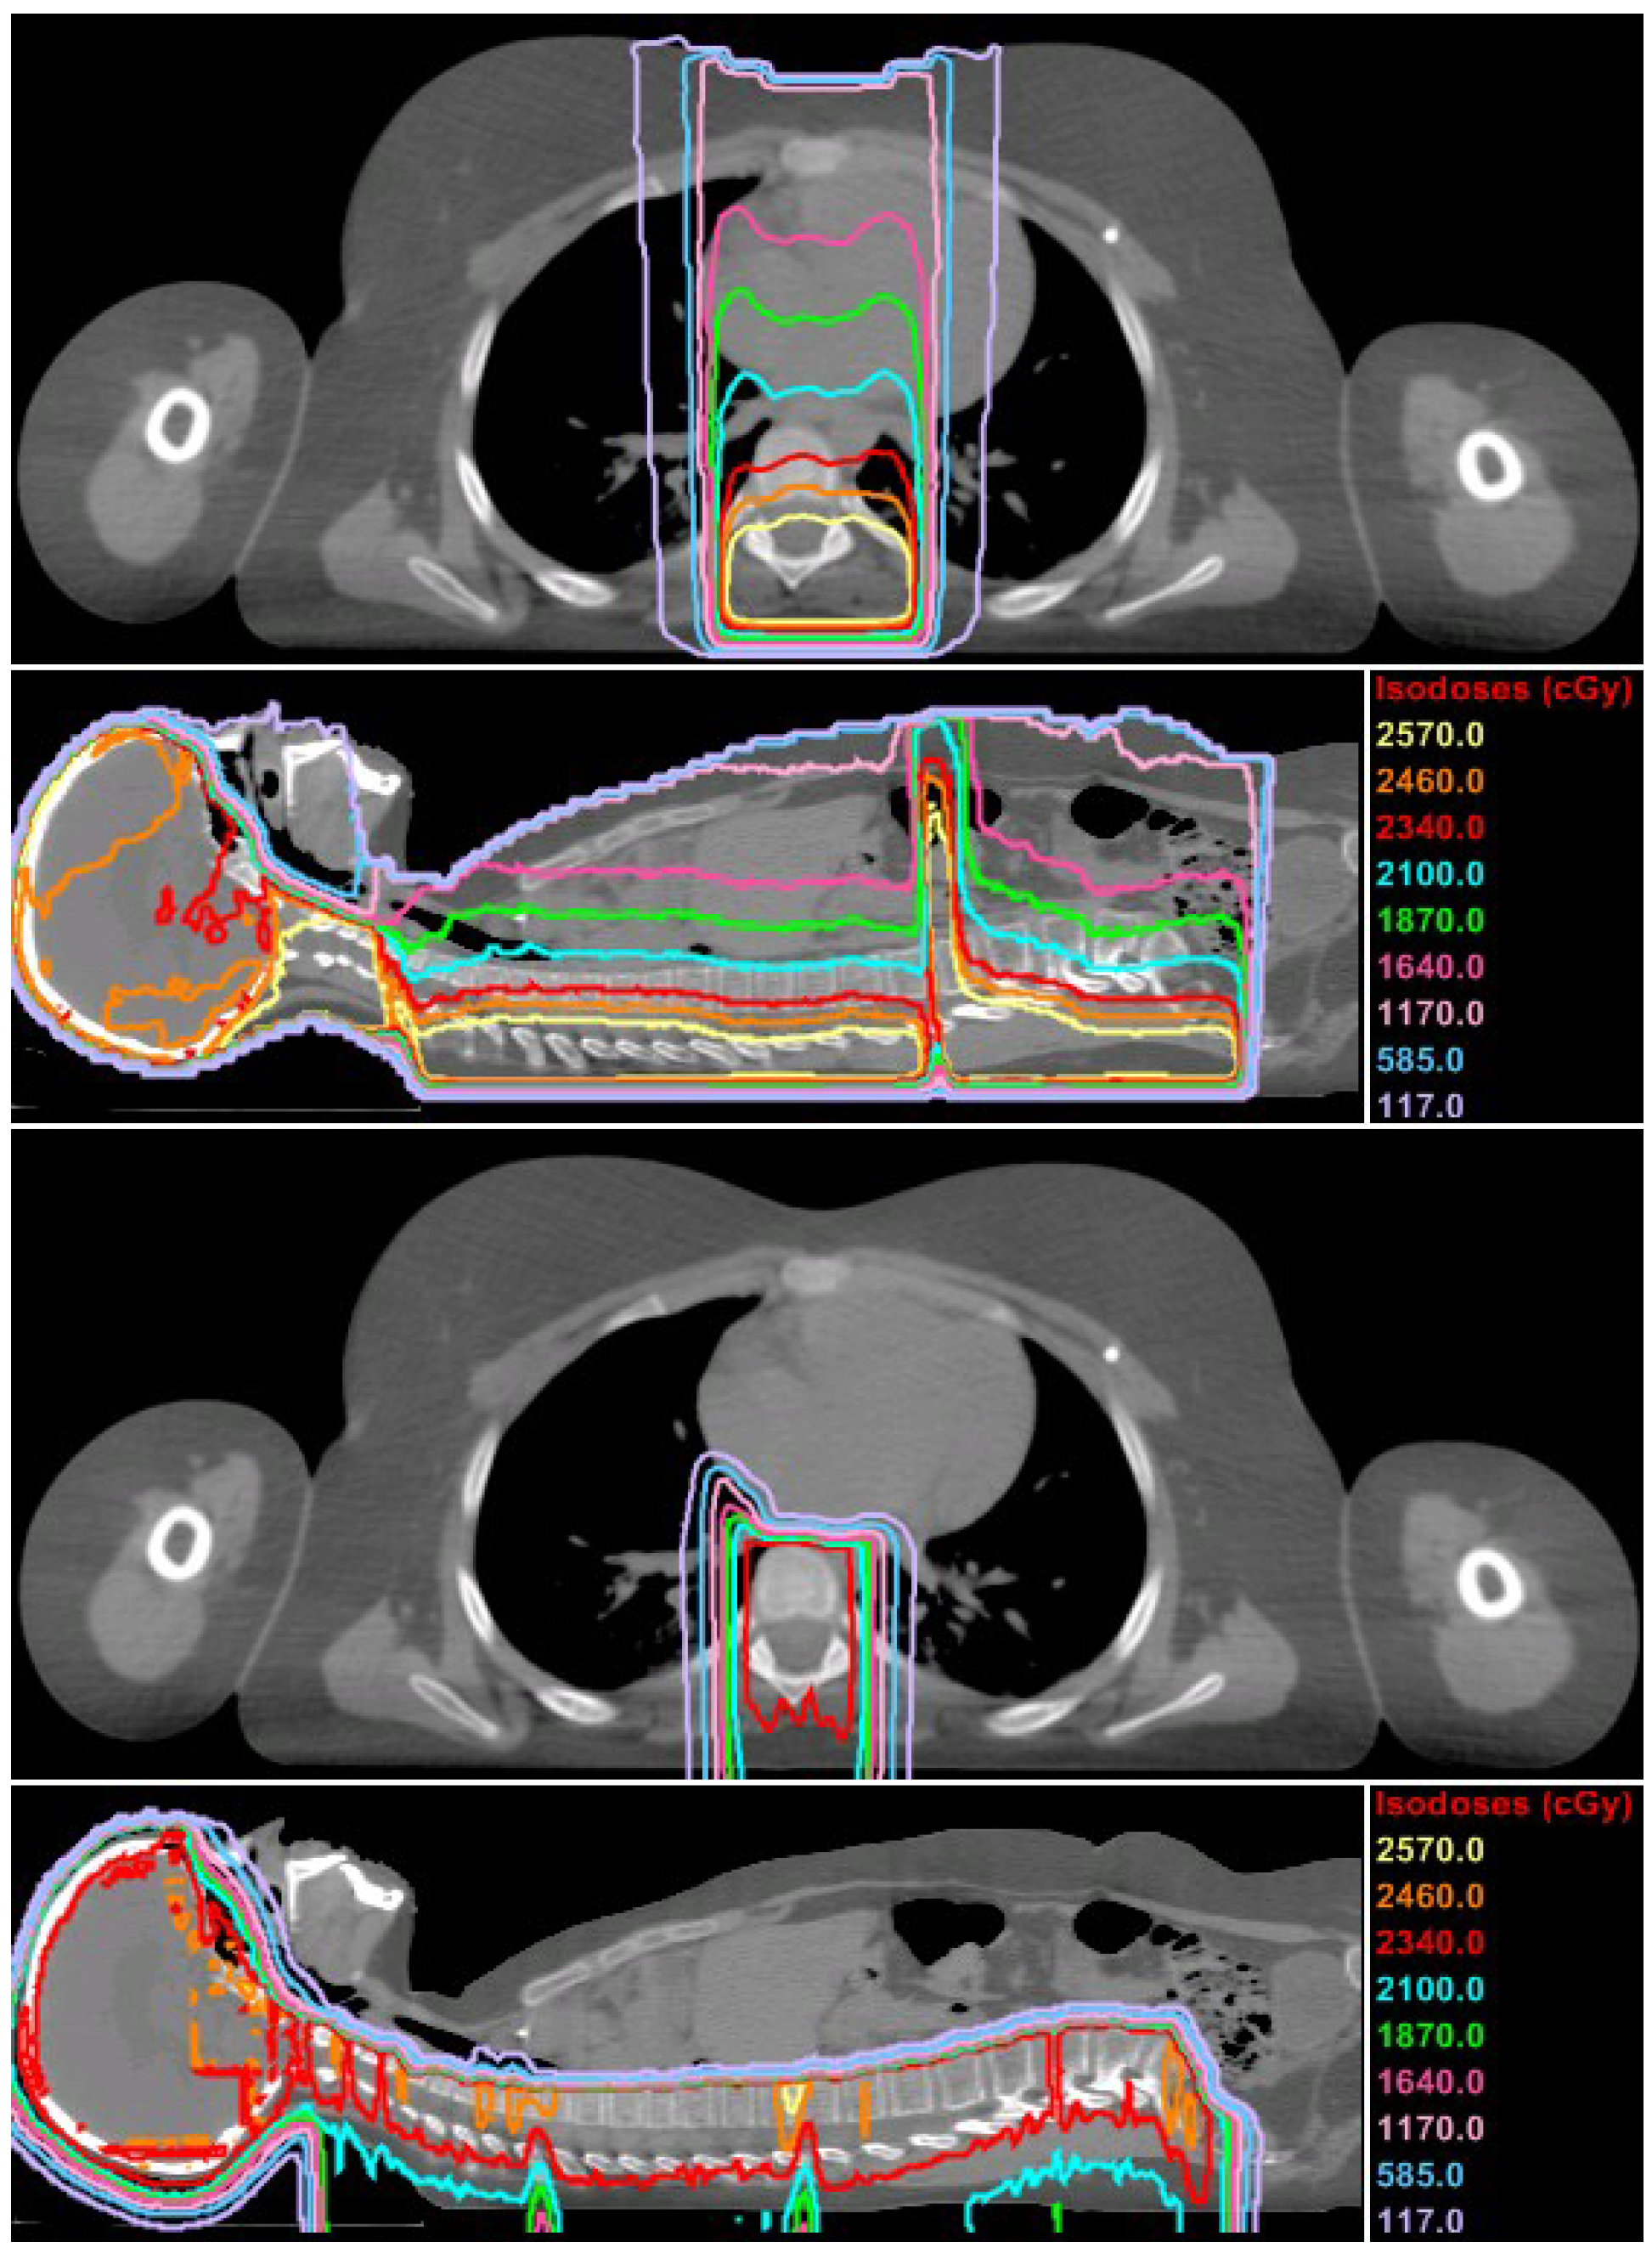

2.1.2. Photon CSI

2.4.1. Approach 1: TPS Calculations

2.4.2. Approach 2: Volume-Weighted Average

2.4.3. Approach 3: Model-Based Estimate